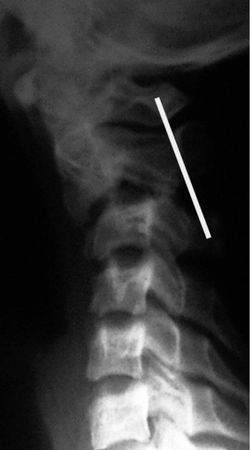

Рис. 4.4. Истинный травматический передний вывих CII у ребенка 16 лет. Линия Swischuk не нарушена (дуга CII не сломана). Имеется разобщение суставных поверхностей CII–CIII. Смещение CII кпереди и вниз на Vi тела CIII